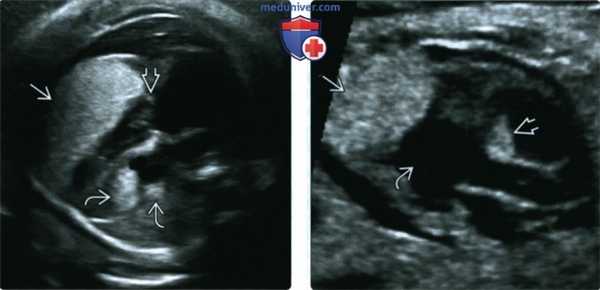

(Слева) Четырехкамерный срез сердца. Определяется очень крупное образование, поражающее всю свободную стенку ПЖ. Опухоль не вызывает обструкцию входного отдела, о чем свидетельствует отсутствие изменений ТК. В области верхушки ЛЖ визуализируются другие образования.

(Справа) Срез по длинной оси. Определяются крупное образование в области верхушки ЛЖ и небольшое образование в толще перегородки. Полость ЛЖ не уменьшена, обструкция входного или выходного отделов отсутствует. В данном случае рабдомиомы регрессировали после рождения ребенка.